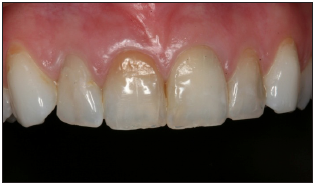

Maxillary anterior view

Center the maxillary anterior teeth using the frenum and midline as references. The lips should not be visible.

No retractors should be visible. The gingiva adjacent to the teeth should be visible. The opposing teeth should not be visible.

A contrasting or background device may be used to block out images of mouth and tongue.

Image should be captured at 90 degrees to the patient and directly in front.

The maxillary four to six teeth should be captured.